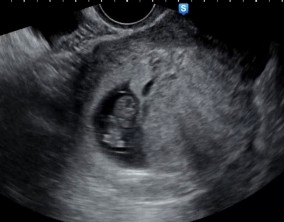

심장소리 이후, 함께 웃게 된 임밍아웃